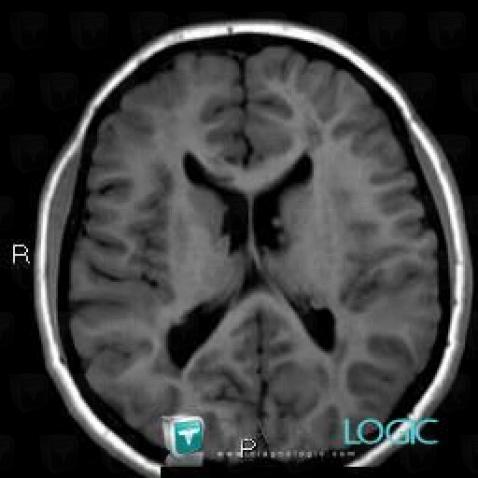

Here is the specific information in the key image above:

- Diagnosis Tuberous sclerosis (link to Hamartoma), Location(s) Ventricles / Periventricular region, with gamuts Periventricular anomaly seen in MRI, Ventricular wall nodules

Here is the specific information in the key image above:

- Diagnosis Tuberous sclerosis, Location(s) Ventricles / Periventricular region, with gamuts

- Diagnosis Hamartoma, Location(s) Ventricles / Periventricular region, with gamuts Periventricular anomaly seen in MRI, Ventricular wall nodules